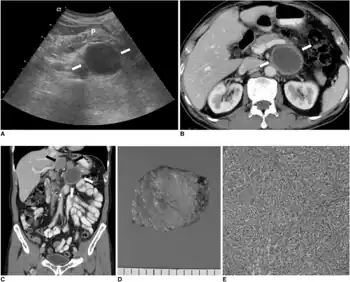

| Micrograph showing a follicular dendritic cell sarcoma. The cancer cells are larger and have pale staining nuclei. The smaller (benign) interspersed lymphocytes (darker blue) are common and suggest the diagnosis. H&E stain. | |